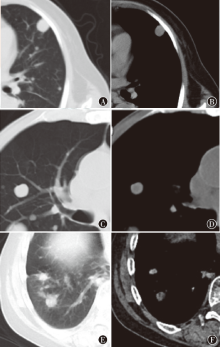

Xiong Min, Chen Yi, Wang Jianbo. Value of CT radiomic features in differential diagnosis of lung metastases[J]. Journal of International Oncology, 2023, 50(4): 208-213.